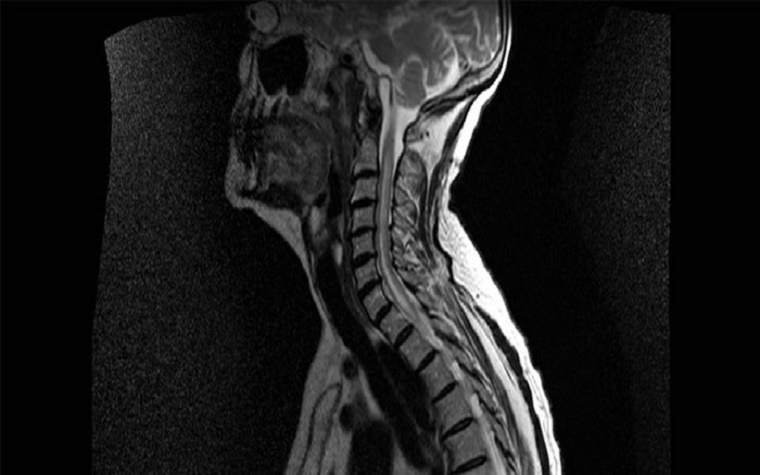

There is no cure nor approved medications for NMO, which attacks the central nervous system and can be fatal. NMO patients' healthy cells are attacked by their own immune systems. The condition typically affects the optic nerves and spinal cord and is diagnosed in approximately five of every 100,000 people.